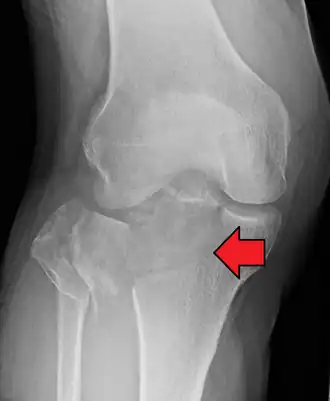

Una fractura de meseta tibial vista con rayos-X

En todas las lesiones a la meseta tibial es imperativo efectuar radiografías (generalmente llamados rayos X). Las tomografías computarizadas no son siempre necesarias pero algunas veces son indispensables para evaluar el grado de fractura y determinar un plan de tratamiento que no sería posible con simples radiografías. Las imágenes de resonancia magnética son la modalidad de diagnóstico preferidas cuando se sospechan fracturas de menisco, ligamentos y/o tejidos. La angiografía-TC debe ser considerada si existe una alteración de los pulsos distales o cuando exista preocupación de una lesión arterial.

Diagnóstico